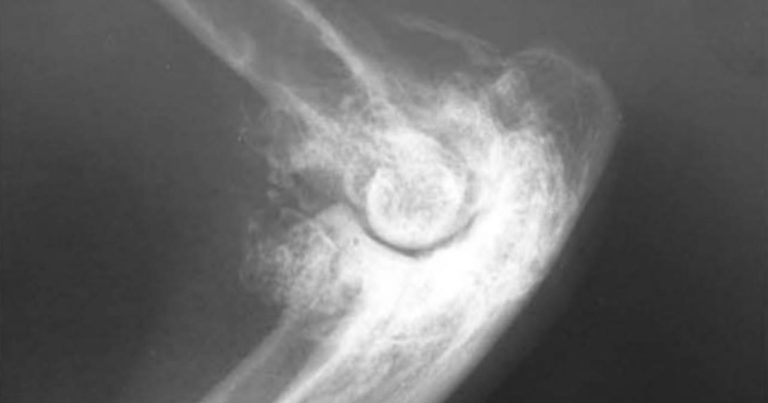

Figure 1. Severe bone remodelling in the elbow of a cat with arthritis.

Painful joints may be radiographically normal, and joints exhibiting extensive bony remodelling (Figure 1) may appear quite comfortable on physical examination. In a study of 13 cats whose owners recognised that they had impaired mobility, 33% of joints had evidence of both pain on manipulation and radiographic change while 67% of joints had radiographic evidence of DJD, but no apparent pain on manipulation (Lascelles et al, 2007).